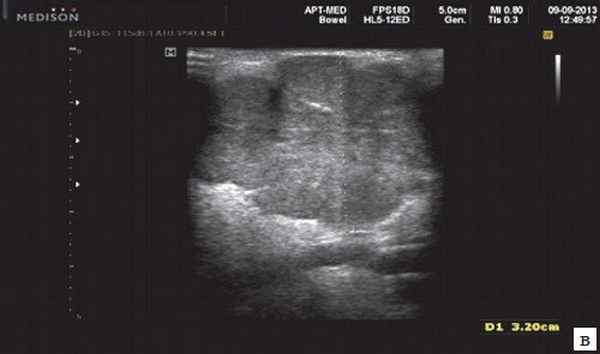

- обструктивные сиаладениты, развивающиеся при затруднении оттока слюны при обструкции выводного протока камнем (рис. 5-7) или сгустившимся секретом, а также вследствие рубцового стеноза протока. По распространенности процесса различают очаговый, диффузный сиаладениты и сиалодохит - воспаление выводного протока. Течение процесса может быть острым и хроническим;

Рис. 5. Камень протока поднижнечелюстной слюнной железы.

Рис. 6. Камень в паренхиме поднижнечелюстной слюнной железы.

Рис. 7. Камень в протоке поднижнечелюстной слюнной железы.